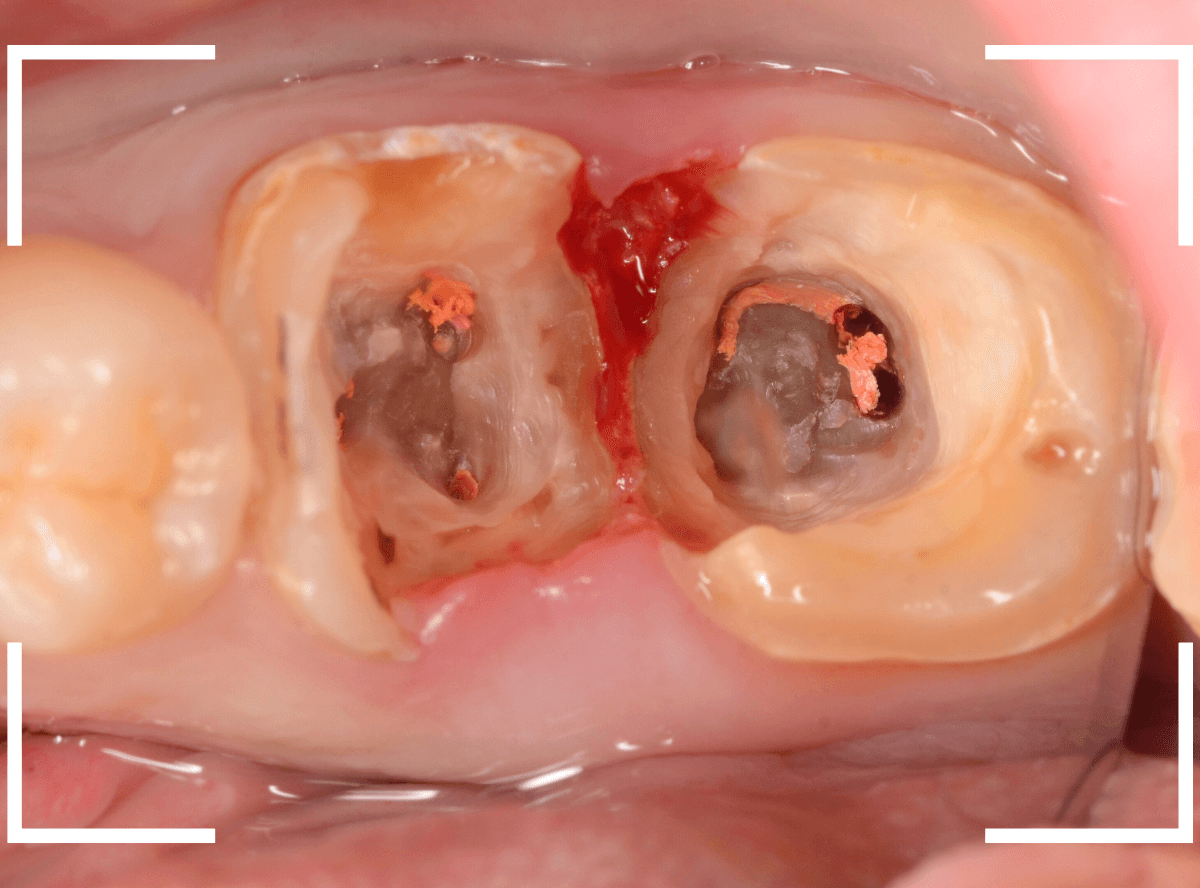

Case.15 歯肉の中まで、虫歯が進行

今回は、下の奥歯が虫歯になってしまった方です。

銀歯の下が大きくかけていますが、神経を取っている歯なので痛みはありません。

隣りの奥歯は、土台のまま治療途中になっています。

レントゲン写真で確認します。

赤い部分が虫歯、青い線が歯肉のラインです。

奥歯2本とも虫歯になっています。

どちらも虫歯が深く、歯肉の中まで入り込んでいると思われます。

この虫歯の深さは、最悪、抜歯が必要になるかもしれないケースです。

神経のない歯ですが、歯肉を処置する必要があるため、麻酔をして治療します。

まず、つめものを外します。

歯肉を処置しながら、虫歯を除去します。

虫歯の全て除去後、止血したところです。

かなり深いところまで虫歯が進行していましたが、なんとかぎりぎり抜歯せずに、土台を作って噛み合わせを回復できそうです。

神経を取った歯は、虫歯がいくら進行しても痛みにならず、最悪、抜歯一直線になってしまいます。